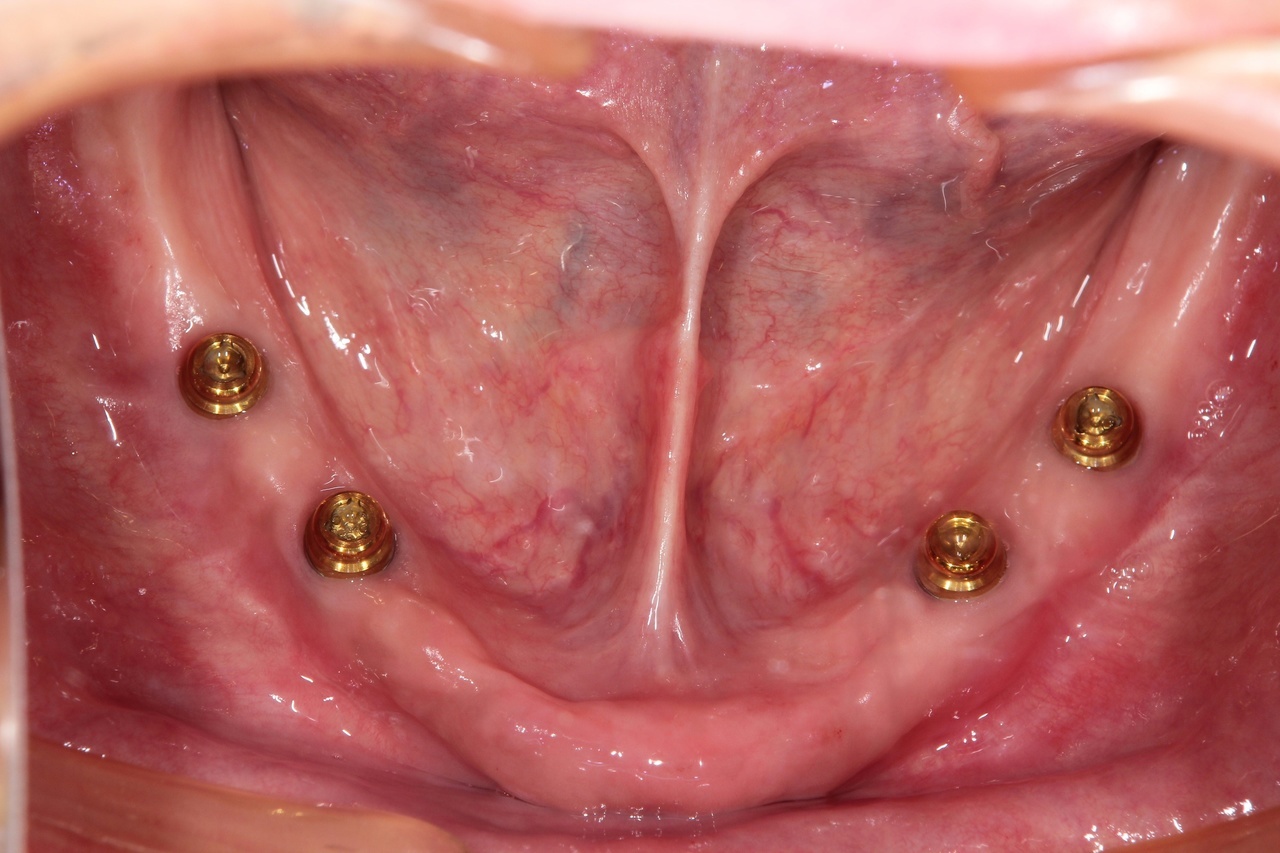

インプラントオーバーデンチャー<ロケータータイプ> (沼津市在住 男性)

インプラントを埋め込み、固定用のロケーターを装着し、入れ歯をしっかりと固定する治療法です。

少ない本数でがっちり噛める治療法です。取り外し可能でしっかり固定できるので、入れ歯の誤飲の心配がなく、手入れがしやすいので寝たきりになっても安心に使用出来ます。

しっかり噛むことで踏ん張りがきくので転んで骨折するリスク回避にもなります。

● オーバーデンチャーを外した状態

● オーバーデンチャーを付けた状態

インプラントオーバーデンチャー

インプラント4本+入れ歯:2,100,000円+税

静脈内鎮静法:0円

上顎と下顎に、インプラント4本+入れ歯、を作る場合 総額:4.200.000+税

骨の条件が良ければ、下顎の場合はインプラントの本数を減らすことができます。

【インプラント2本+入れ歯】1,550,000円+税

【インプラント3本+入れ歯】1,825,000円+税